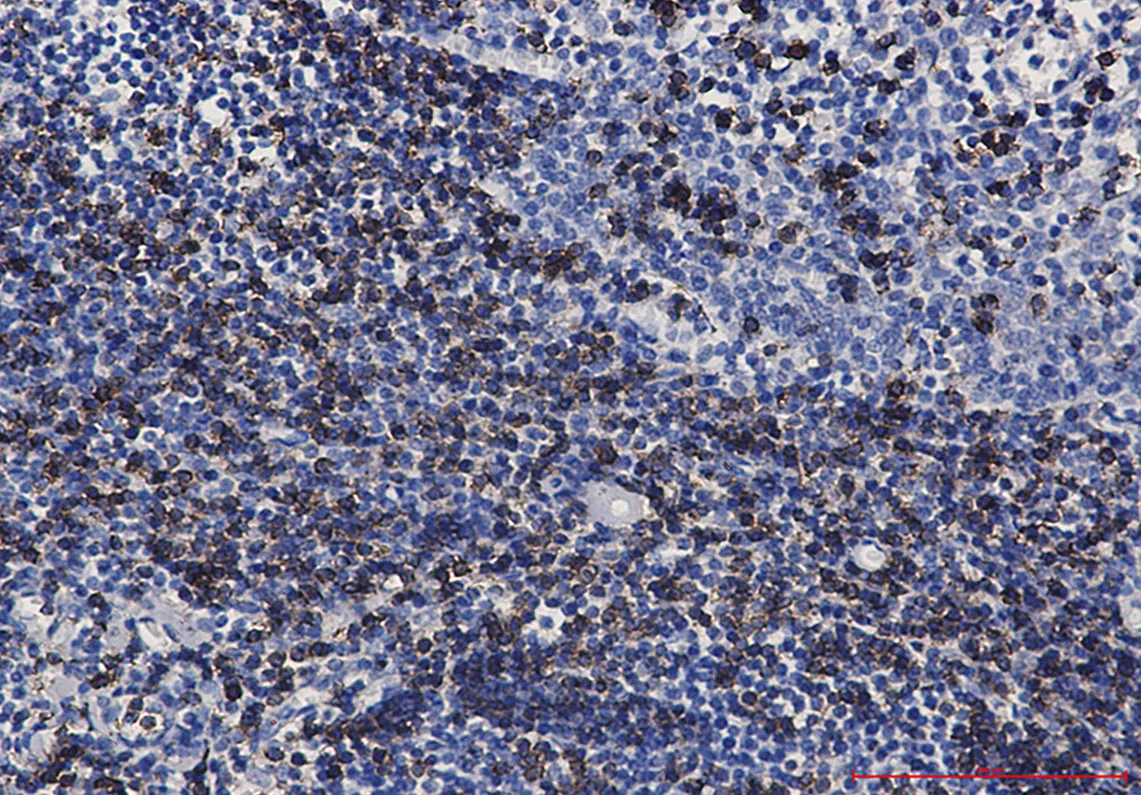

CD7 Rabbit Monoclonal Antibody

Cat: AMRe01799